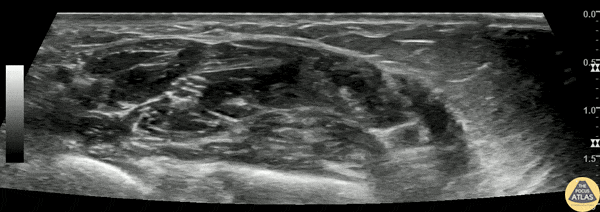

60s F presented with intractable wrist pain due to known carpal tunnel syndrome. The patient was already established with hand specialist followup and had failed multiple other analgesics including a steroid course. To aid in analgesia, a median nerve block was performed. Shown here, the median nerve (*) is seen in the forearm, in the fascia plane between the flexor digitorum profunda and flexor digitorum superficialis muscle bellies. Anesthetic was injected in this fascial plane, adjacent to the median nerve. The patient had significant pain relief and was able to be discharged with hand specialist follow up. Dr. Nimish Bhatt, Fellow Denver Health Ultrasound Fellowship